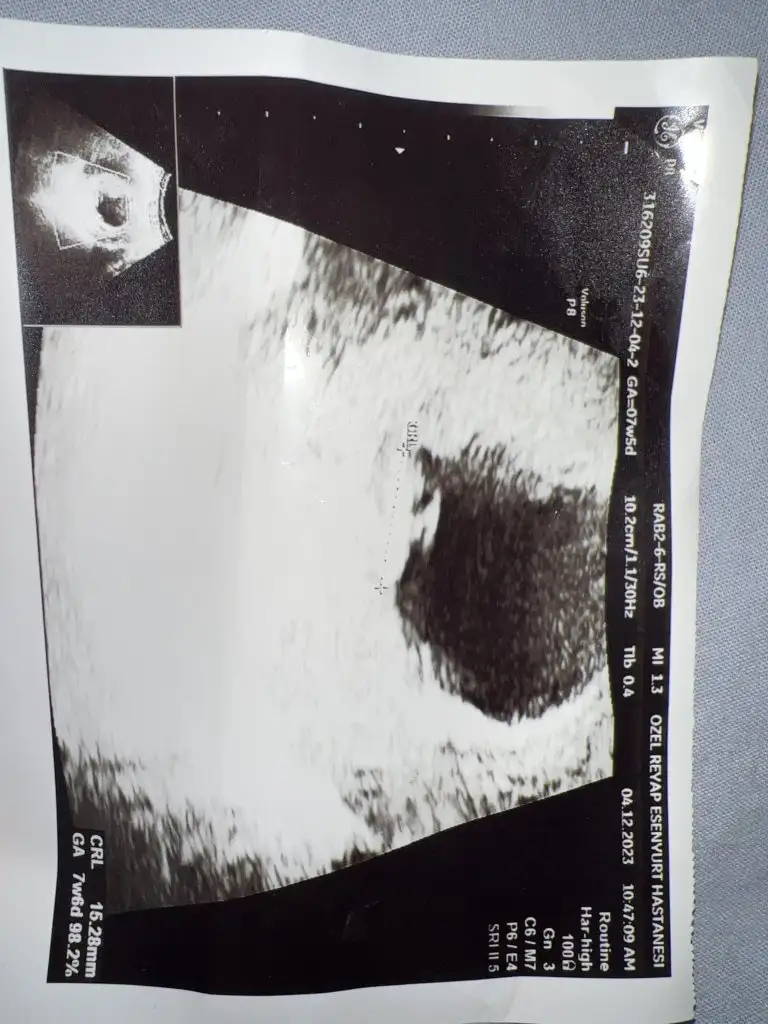

Banada bakabilir misinz 7+5 karındanKarından ultrasonsa erkek

Karından ultrasonsa erkek

Bence keseye göre kız,yuvarlak çünkü benim üç gebeliğimdede kese yuvarlak değildi ve üçüde erkek

Bende gondersem yorumlarmisinizHayırlı olsun öncelikle , bu ilk ultrason görüntüsü ise erkek bebek tutunma şekligönlünüzden geçen sağlıkla gelsin

Hayırlı olsun öncelikle , bu ilk ultrason görüntüsü ise erkek bebek tutunma şekligönlünüzden geçen sağlıkla gelsin